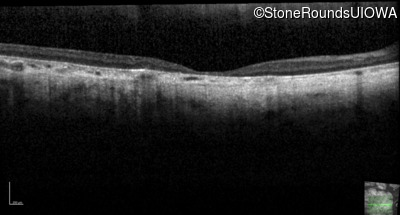

Optical Coherence Tomography - Right - 20/200 +1 sc

Exemplar / OCT Stack

OCT Stack